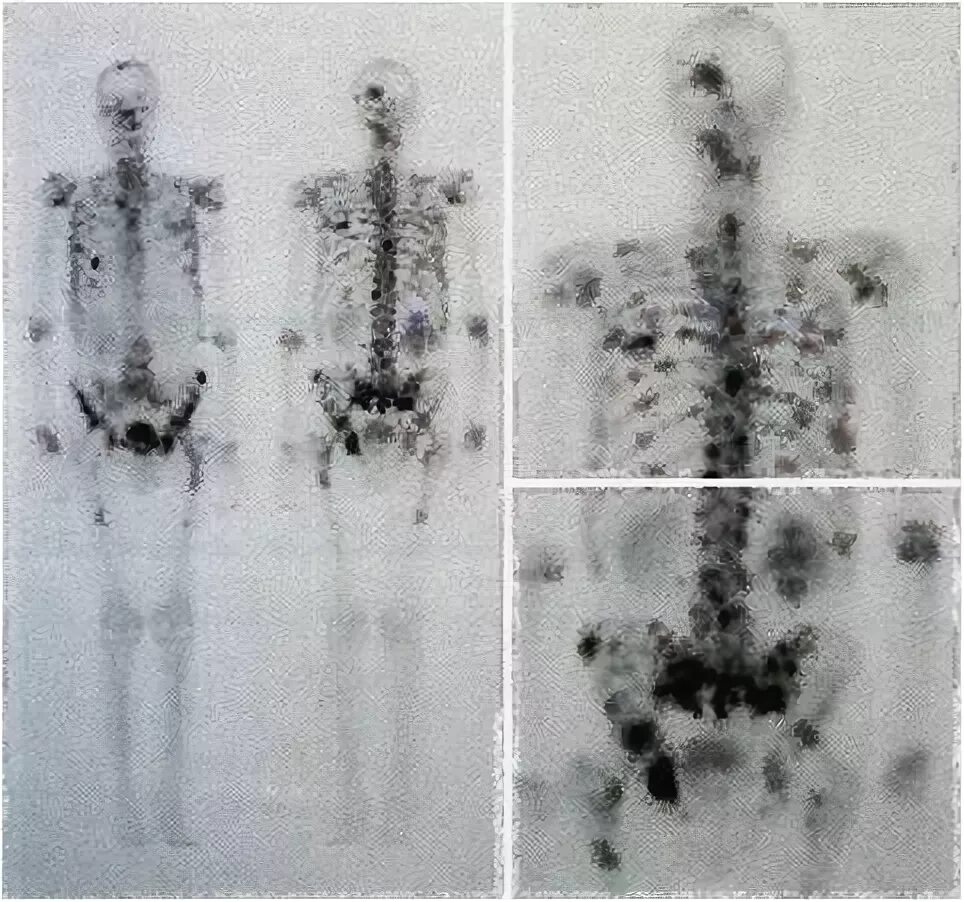

Метастазы костей можно вылечить